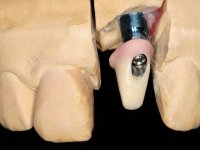

In the initial phase, it was proposed to the patient to perform the surgical implant exposure and after clinical evaluation, make prosthetic decisions. Once the healing screw was placed and the soft tissues were healed, an inadequate position of the implant was found. In view of the dramatic situation, the patient was proposed to remove the implant and put a new one after tissue regeneration. This proposal was rejected by the patient, who suggested temporary rehabilitation of the current implant. A new proposal was then made, to rehabilitate the implant, consisting of a screwed abutment, and on this, the placement of an acrylic crown with coronal and gingival components. After 6 years with the provisional treatment, the patient appeared in consultation with an abscess in tooth 1.1. After clinical and imaging analysis, it was decided to remove teeth 1.1 and 2.2, submerge the implant, place two implants at the site of 1.1 and 2.2 and perform adequate tissue regeneration. Temporization would be done with a provisional 3-element bridge, adhered with a net to the neighboring teeth. After osseointegration, definitive rehabilitation would be done with a 3-element bridge, including zirconia infrastructure and ceramic cover.

The surgical implant exposure and the healing screw placement proved to be a negative surprise regarding its position. Since the proposed removal of the implant was refused, we advanced to its provisional rehabilitation. An open tray impression technique was done, and a screwed abutment with a coronal and gingival component and an acrylic crown were made in the laboratory, using these two components. The provisional crown was placed in the mouth until a final decision was made. Six years passed before the patient returned to the clinic with an abscess on tooth 1.1. The choice to remove teeth 1.1 and 2.2 was made, to create a provisional 3-element bridge with a net to be adhered to the adjacent teeth. Surgery was planned and performed, placing the two implants at the site of 1.1 and 2.2, and the implant at the 2.1 site was cut with the objective of submerging it, while adequate tissue regeneration was performed (Surgical Work performed By Dr. Manuel Neves). During osseointegration, the patient used the fixed provisional bridge. A first impression was made for confection of a zirconia screwed provisional bridge, which worked the soft tissues for twelve weeks. The definitive impression was made with the individualisation of custom impression copings. Final rehabilitation was done with ceramized abutments, and also a bridge with zirconia infrastructure and ceramic cover. Due to the inclination of the implant placed at the site of tooth 1.1, the bridge required cemented fixation.